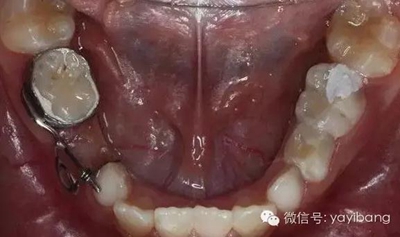

36、放回模型試合,合面觀

37、放回模型試合,頰面觀

38、取下帶環(huán)、推簧加力

39、推簧加力后合面觀

40、加力后,重新就位合面觀